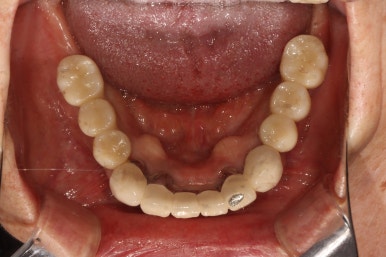

저희 치과와 협업하는 기공소에서 제작해온 임시치아를 장착한 상태입니다.

플라스틱 재질인 레진으로 제작되어 있어 색상은 그닥 수려하지 않으나, 연습용으로 써보기에는 아주 딱이죠?

생각보다 보기에 모양도 괜찮습니다. 요새 임플란트 보철물은 모두 CADCAM으로 지르코니아 블럭을 깎아서 제작하기 때문에, 만약 이 임시치아가 마음에 드셨다면 최종 지르코니아 크라운도 컴퓨터에 입력된 데이터를 이용하여 똑같이 깎아서 제작해드릴 수 있답니다. 이 모든게 치과에서 구강스캐너를 사용하기에 가능하죠..

어쨌든, 어금니 임플란트로 치아가 6개나 새로 제작되었기에 볼이나 혀가 씹히진 않는지 - 식사시에 아프거나 음식이 끼는 것은 없는지 등을 확인하기 위해 약 2-4주 정도 사용해보시게 됩니다.

생각보다 임시치아보다 훨씬 매끈한 표면과 비슷한 색깔을 자랑하는 지르코니아 크라운입니다.

아마 어금니에 임플란트가 생긴건가? 싶으실거에요.

오스템 원가이드 네비게이션 임플란트 시스템을 이용하면, 정교하게 이상적인 위치에 임플란트를 심어낼 수 있어 자연스러운 임플란트 보철물을 제작하는데 많은 도움을 받을 수 있습니다!!

최종 완성된 보철물은 상당히 이상적인 형태를 갖고 있습니다.